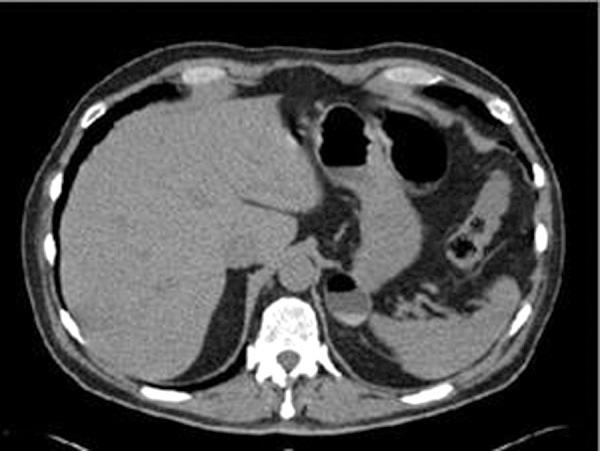

Gastric diverticula are rare and usually asymptomatic. This report, however, describes two examples of symptomatic gastric diverticula successfully treated by laparoscopic resection. Both patients were male and in their sixth decade of life. One patient was relatively healthy with no past medical history, whereas the other patient had chronic pain issues and at presentation was also undergoing evaluation for hyperaldosteronism. The patients presented with gastrointestinal symptoms, including nausea, emesis, abdominal pain, and change in bowel function. In both cases, a gastric diverticulum was identified by CT scan, and precise anatomic position was determined by upper endoscopy. After discussion with the treating teams, including a gastroenterologist and surgeon, surgical treatment and resection was elected. Successful laparoscopic removal was accomplished in both patients, and they were discharged home after tolerating liquid diets. Both patients reported resolution of their abdominal symptoms at follow-up.

https://cdn.ncbi.nlm.nih.gov/pmc/blobs/661c/3939326/9641358d5991/jls0031331140001.jpg